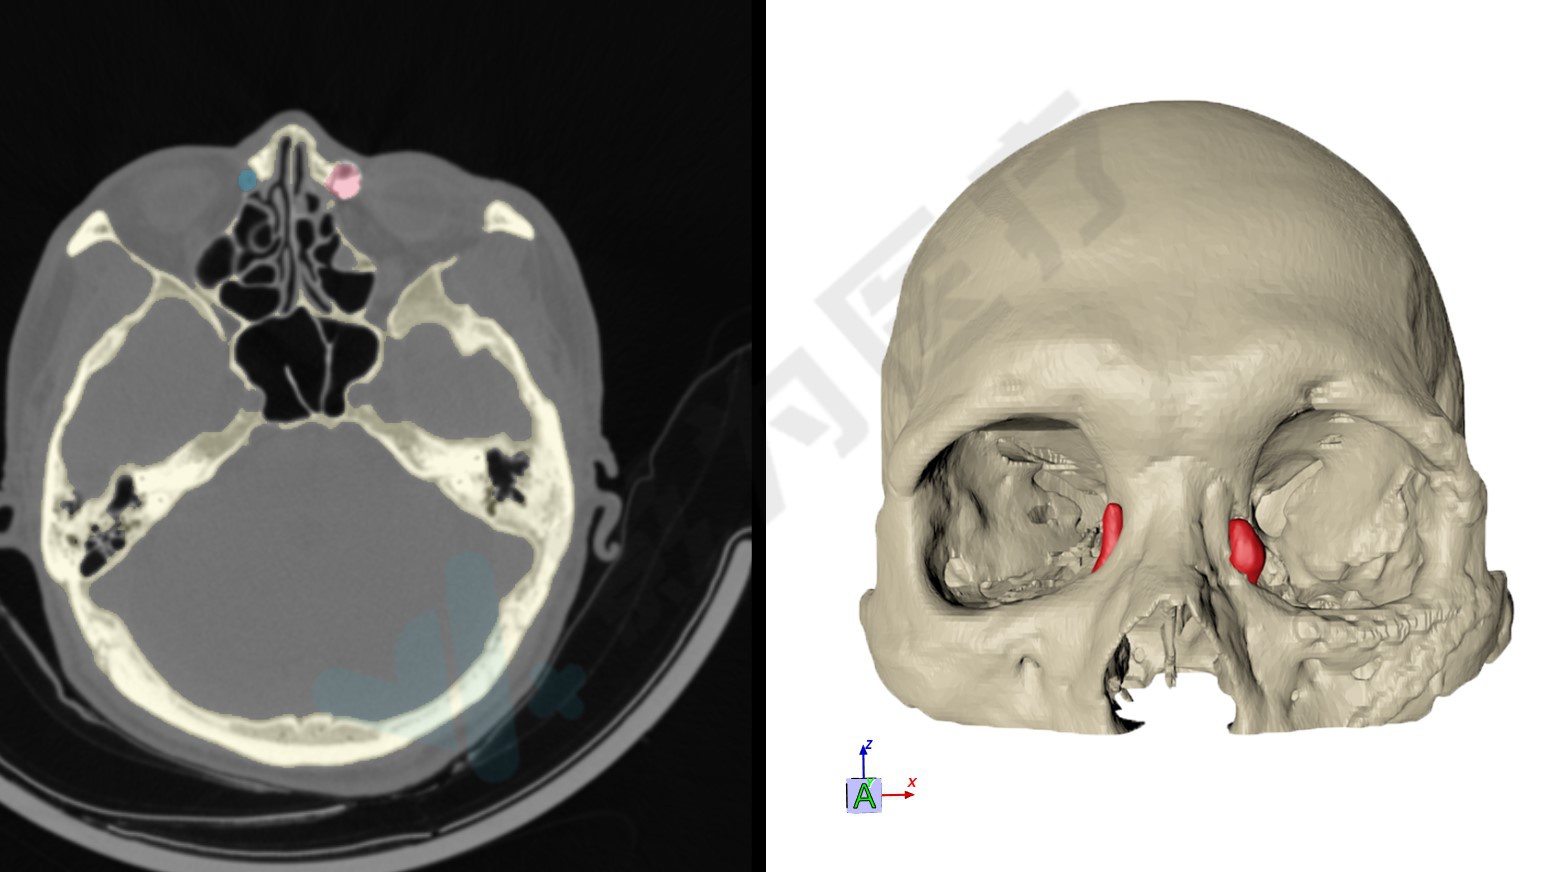

患者术前头颅三维ct颅骨扫描

头颅ct三维渲染.